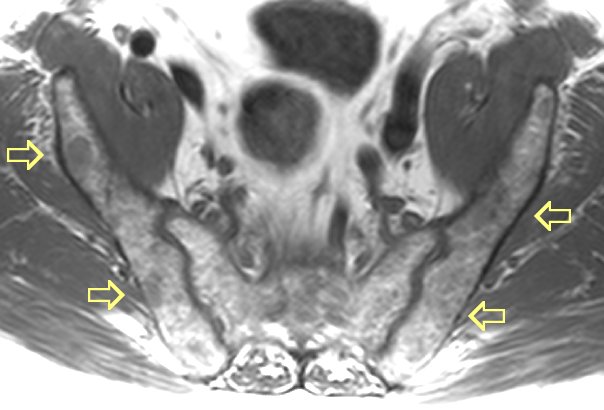

#7 MRI images of very diffuse disease

here and

here